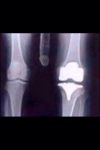

You may not have heard but I have recently had to have my left knee replaced.

It was all a bit sudden but I was getting quite a bit of pain.

The Specialist said it was arthritis caused by old Rugby injuries and prospecting.

I am still on crutches, it is a lot better and I no longer have any stiffness.

The Hospital has sent me a copy of my XRay of the replacement..below....and all looks better than most.....